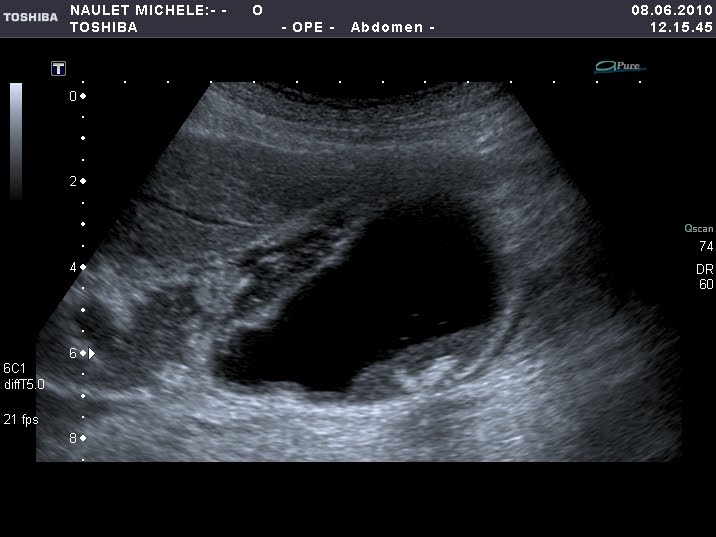

ez csak egy szep cholecystitis

- Cholecystitis